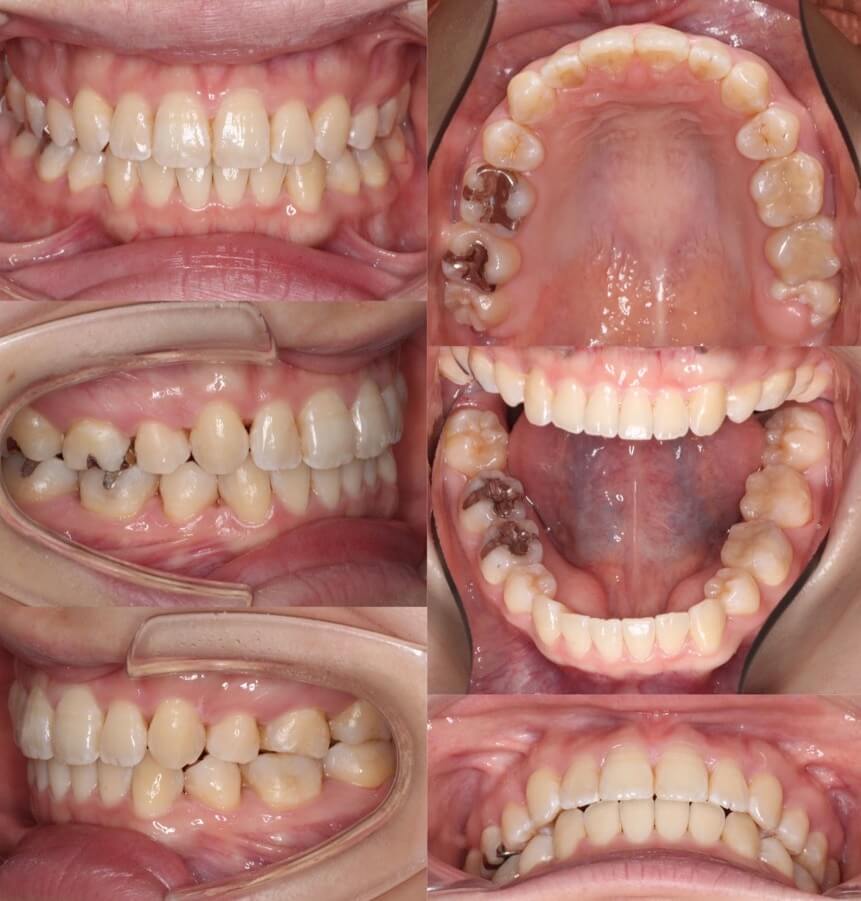

「美容目的にはリスクが伴う」

20代女性・マウスピース型装置・美容改善型

上の前歯の角度もE-lineも悪くはないのですが、患者さんは横顔での口元の突出感を改善したいということで、マウスピース型装置にて上下小臼歯抜歯矯正治療を行いました。美容目的要素が強くなるため、ほうれい線が深くなったり、ブラックとライアングルが増えるリスクについては事前によく説明しています。治療結果は前歯の後方移動量に対して横顔の変化量は少なめとなり、ちょうど良い形になりました。

<症例概要> 難易度:★★★☆☆

主訴:出っ歯・横顔の突出

年齢・性別:30代女性

住まい:千葉県船橋市

症状:軽度叢生・下顎前歯唇側傾斜

治療方針:抜歯空隙の閉鎖(中等度固定)

治療装置:マウスピース型矯正装置(アライナー装置)

抜歯:上下左右4番(計4本)

治療期間:1年6か月

アライナー枚数:47+30ステージ

リテーナー:上下クリアタイプ+フィックスタイプ

治療費用:990,000(税込)

代表的副作用:痛み・治療後の後戻り・歯根吸収・歯髄壊死・歯肉退縮